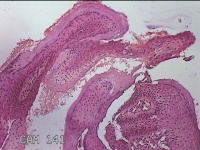

外阴赘生物

性别

女

年龄

33岁

临床诊断

外阴尖锐湿疣

一般病史

发现外阴尖锐湿疣4个月。

标本名称

大体所见

灰白暗红色不规则碎组织0.3x0.2x0.1cm一堆。

良性病变,考虑湿疣。